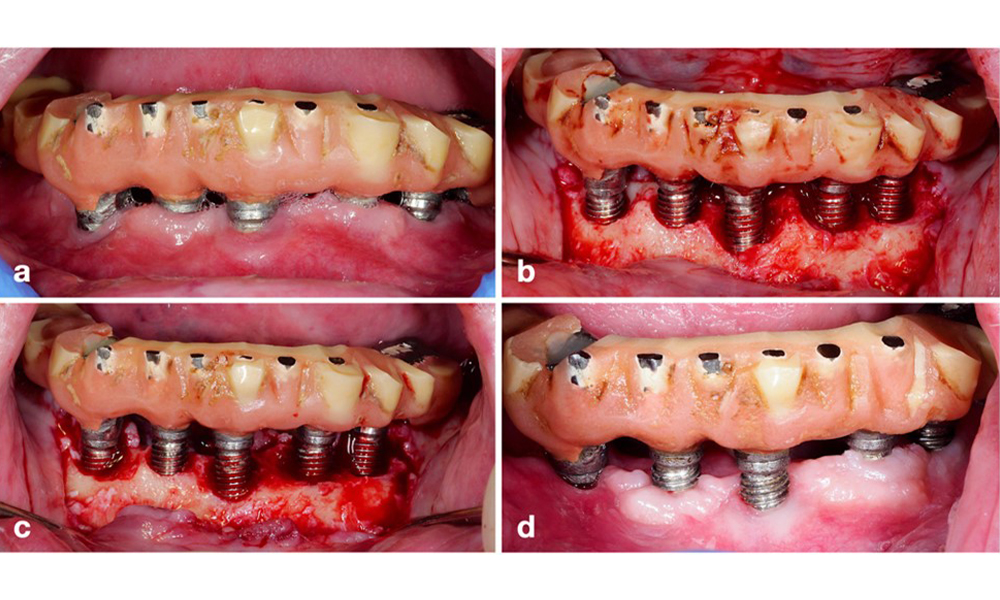

Das Management einer Periimplantitis bei als therapierbar eingestuften Implantaten besteht aus einer nicht-chirurgischen Phase, oftmals gefolgt von einer chirurgischen Intervention. Bei den nicht-chirurgischen Verfahren kommen ähnliche Maßnahmen zum Einsatz wie bei der Behandlung einer periimplantären Mukositis. Laborexperimente lassen darauf schließen, dass Luftpoliergeräte mit subgingivaler Düse bei der Biofilmentfernung im Vergleich zu Hand- oder Ultraschallinstrumenten allem Anschein nach bestimmte Vorteile bieten (Herrera et al. 2023; Moharrami et al. 2019; Ronay et al. 2017) (Abb. 9).

Allerdings gibt es bei den nicht-chirurgischen Verfahren häufig Einschränkungen beim Zugang zur Implantatoberfläche mit der Folge einer unzureichenden Dekontamination. Das zeigt sich auch in der klinischen Praxis: Die Heilung nach einer nicht-chirurgischen Behandlung der Periimplantitis ist eher unvorhersehbar. In den meisten Fällen kommt es zu einem Rezidiv und nur in weniger als jedem zweiten Fall zur Heilung (Ramanauskaite et al. 2021). Aus diesem Grund muss das Ergebnis einer nicht-chirurgischen Behandlung nach etwa 6 Wochen evaluiert werden und bei moderater oder fortgeschrittener Periimplantitis ist von der Notwendigkeit eines chirurgischen Eingriffs auszugehen.

Die prothetische Restauration sollte bei einer nicht-chirurgischen ebenso wie bei einer chirurgischen Behandlung abgenommen werden, um einen besseren Zugang zur Implantatoberfläche zu ermöglichen. Die Wahl der chirurgischen Intervention (z. B. resektiv, rekonstruktiv oder eine Kombination) hängt von mehreren Faktoren ab: (1) Morphologie des Defekts (z. B. horizontal, Dehiszenz, intraossär oder eine Kombination) (Abb. 10), (2) Implantatoberfläche (also gedreht oder modifiziert/„rau“) und (3) Vorhandensein oder Fehlen einer ausreichend keratinierten und anhaftenden Schleimhaut.